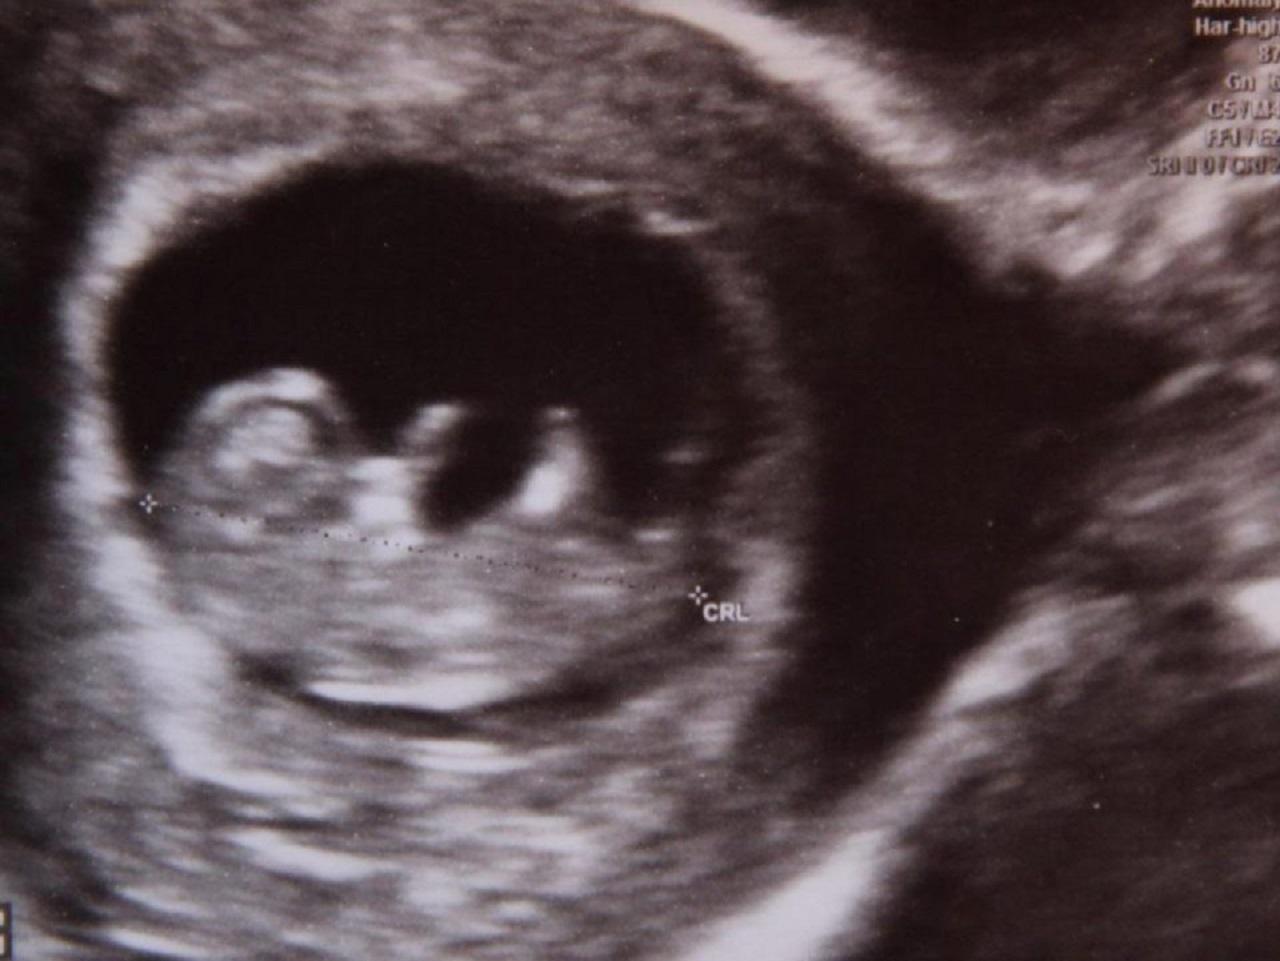

Un tânăr de 21 de ani scrie istorie! Este primul britanic care a dat naştere unei fetiţe